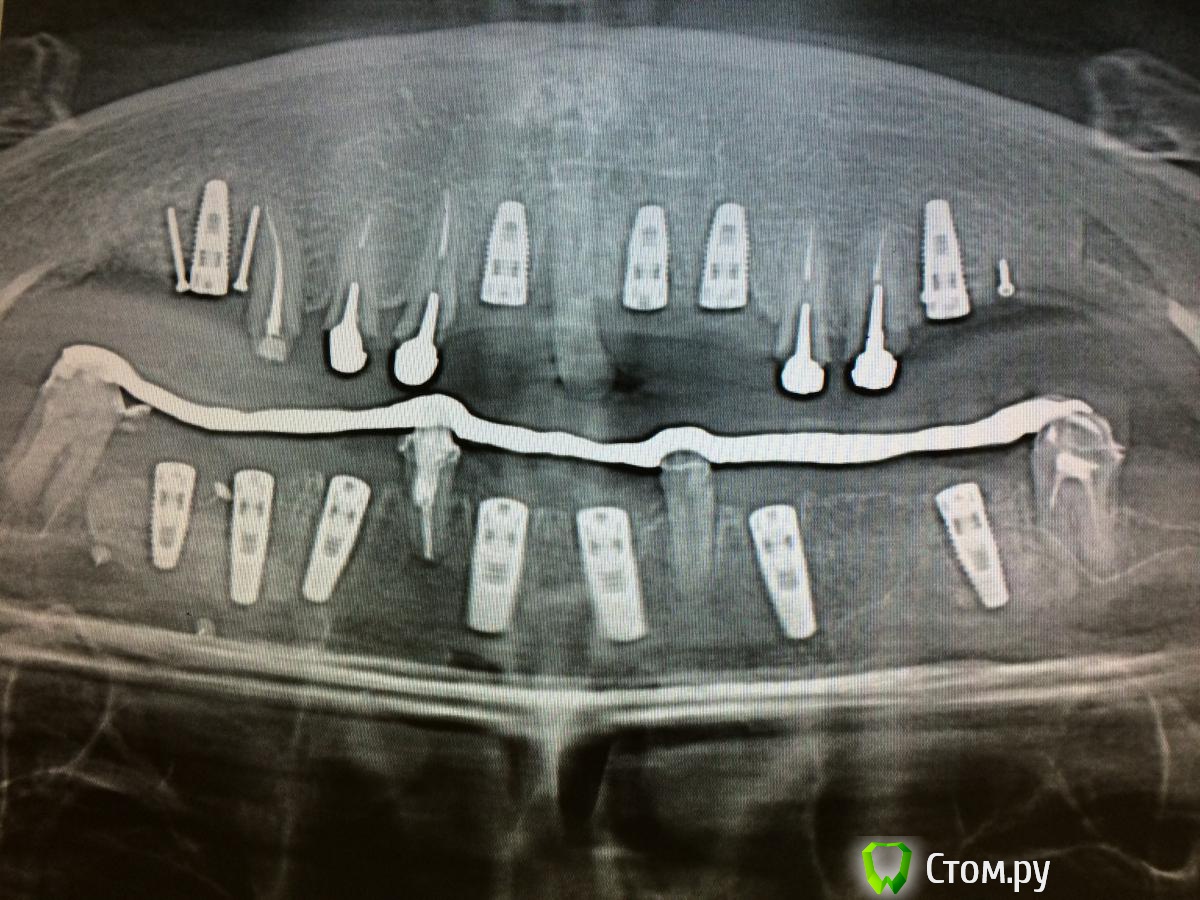

Mbegiev Опубликовано 28 ноября, 2014 Поделиться Опубликовано 28 ноября, 2014 (изменено) 2 синуслифтинга, 2 костных блока, времянки с опорой на свои зубы.Жду комментариев.P.S.: почему-то фото "после" перевёрнуто Изменено 28 ноября, 2014 пользователем Mbegiev 4 1 Ссылка на комментарий

SDC Опубликовано 29 ноября, 2014 Поделиться Опубликовано 29 ноября, 2014 (изменено) Не соглашусь с вами. Единственный зуб, который мог бы оставить, это 23, но смысла в одном этом зубе я не вижу. Уговаривать никого не приходится, предоставили пациенту комплексный план лечения, который его устроил.Смысл в том, что собственный зуб, с сохранными твердыми тканями и работающим пародонтом всегда лучше имплантата, в ближайшем будущем, я думаю, предстоит грандиозная переделка...Такое заключение я сделал на основании контрольного ОПТГ, где риплейсы уже потеряли кость в пришеечной области и имеются корни с вкладками без феррула. Изменено 29 ноября, 2014 пользователем SDC Ссылка на комментарий

Mbegiev Опубликовано 30 ноября, 2014 Автор Поделиться Опубликовано 30 ноября, 2014 (изменено) Смысл в том, что собственный зуб, с сохранными твердыми тканями и работающим пародонтом всегда лучше имплантата, в ближайшем будущем, я думаю, предстоит грандиозная переделка...Такое заключение я сделал на основании контрольного ОПТГ, где риплейсы уже потеряли кость в пришеечной области и имеются корни с вкладками без феррула.Да, я согласен с тем, что здоровый зуб с работающим пародонтом лучше любого импланта. В данной ситуации имела место подвижность I-II степени зубов верхней челюсти. По поводу убыли костной ткани. В этом случае была произведена одномоментная имплантация, и я вижу на снимке не убыль костной ткани, а несформированные лунки, так как орто сделано через месяц после установки.Спасибо за критику. Изменено 30 ноября, 2014 пользователем Mbegiev Ссылка на комментарий